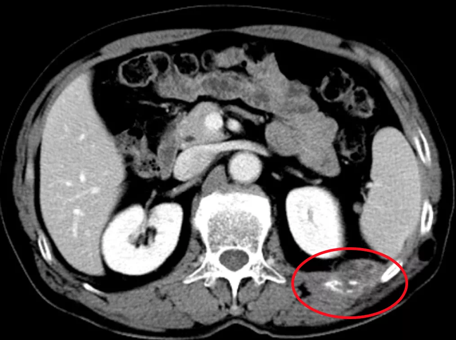

老年男性,68歲,肺癌術(shù)后肋骨轉(zhuǎn)移,痛疼難忍。

左側(cè)肋骨轉(zhuǎn)移